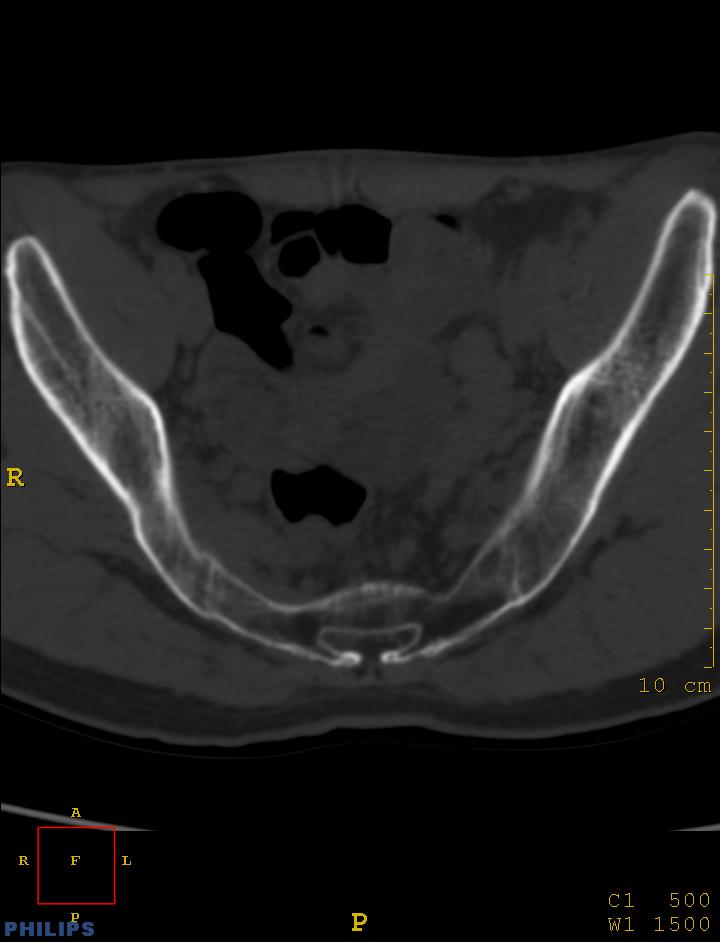

m,34岁,腰痛三年,腰椎活动度明显减低,x片示腰椎竹节样改变

双侧骶髂关节面融合;强直脊柱炎

双侧骶髂关节骨性融合,软骨下囊性变,结合脊柱竹节样改变,典型的强直性脊柱炎。